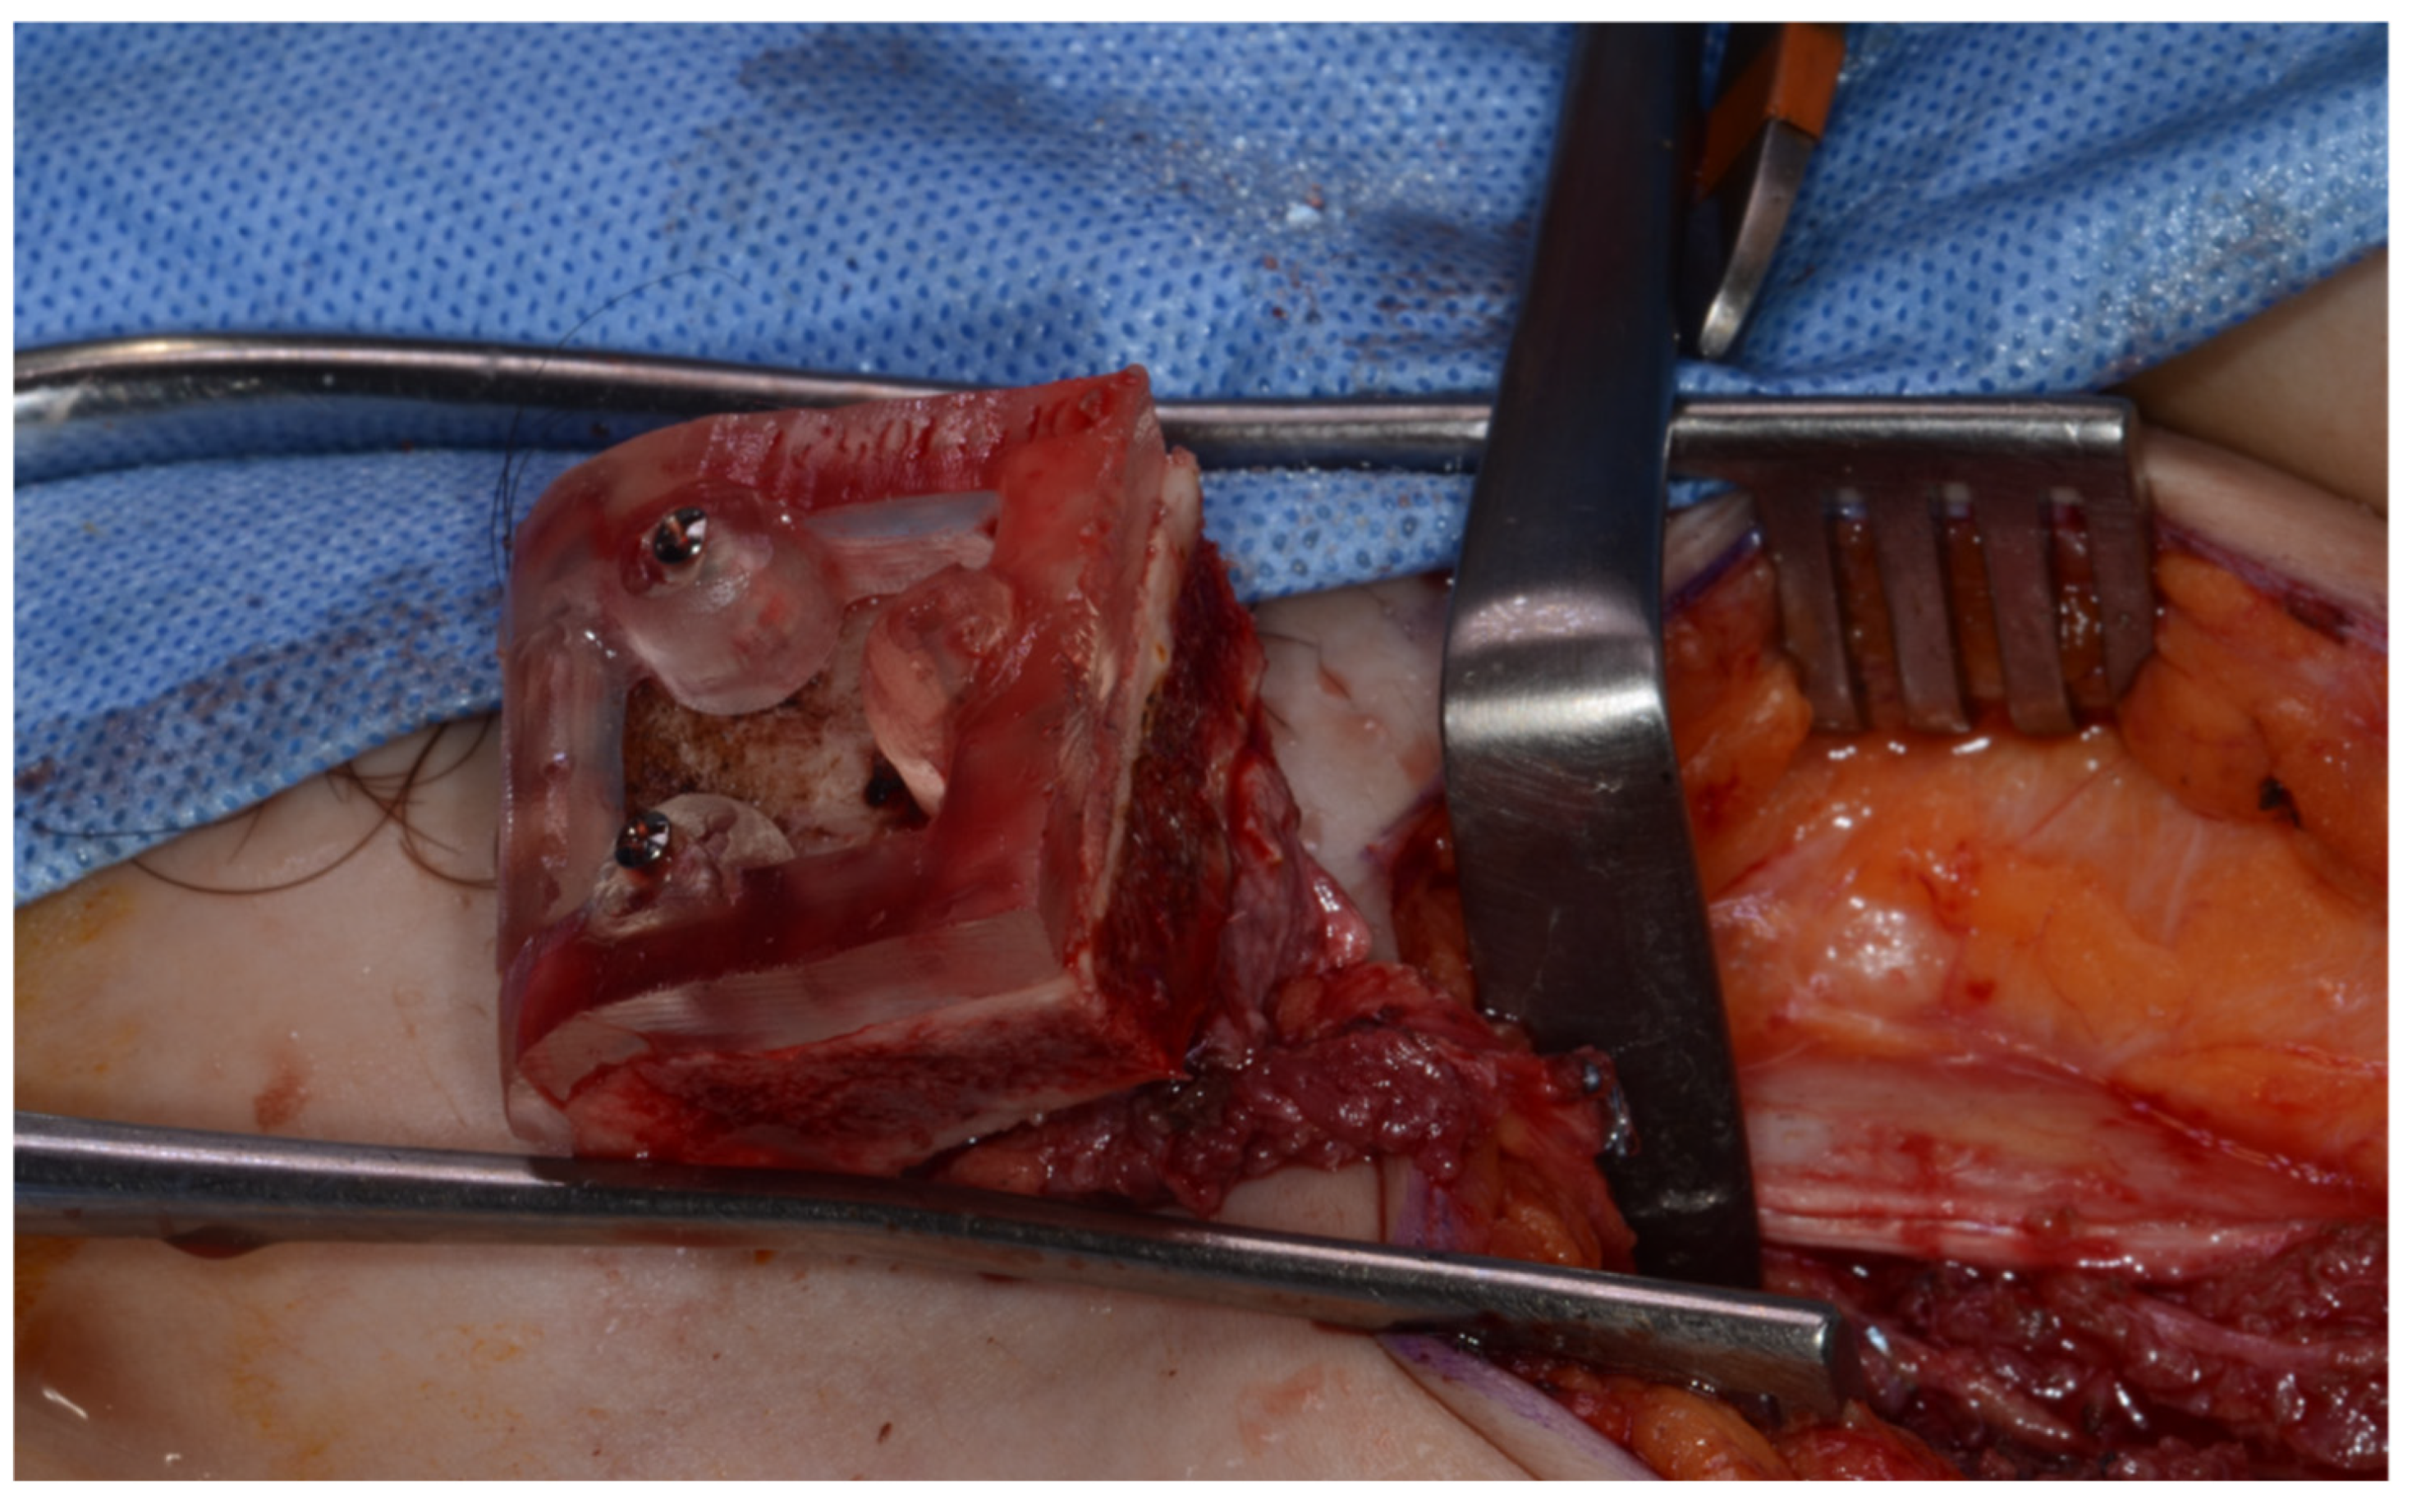

Surgery was performed under general anesthesia. #45, 46, and 47 were extracted. Segmental mandibulectomy was performed using a surgical guide through a submandibular approach. (Figure 6). The left iliac crestal DCIA flap was harvested according to the surgical guide. (Figure 7) To minimize the morbidity of the donor site, the donor site was reconstructed using titanium mesh and allobone chip graft. (Figure 8) Microvascular anastomosis was performed using the facial artery and facial vein. Fixation of the resected mandible and the bicortical iliac bone flap was achieved using a customized reconstruction plate (Cusmedi ©, Sungnam, Republic of Korea) designed to have a thickness of 2 to 3 mm according to the patient’s mandibular morphology and the periphery of the iliac bone flap and 3D printed by the selective laser melting (SLM) method and eight 2.3 mm reconstruction screws. (Figure 9). A silastic drain was inserted into the submandibular region and sutured. (Figure 10) The final diagnosis was ameloblastoma.

Harvested DCIA iliac crestal bone and internal oblique muscle flap with an iliac guide.